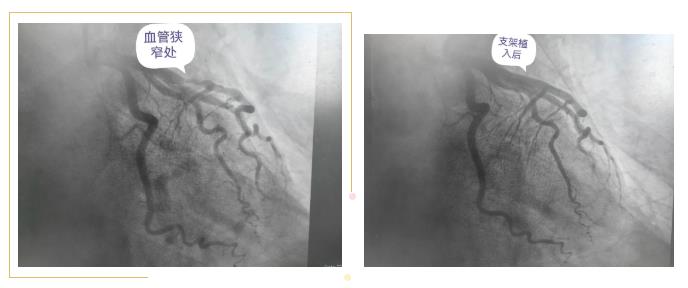

原来前一段时间,张某因“发作性胸闷”入住我院开发区老年科,伴有其他疾病史。住院期间,患者反复发作胸闷,伴大汗淋漓,持续数分钟可缓解,复查心电图较入院时无明显动态改变,心梗三项正常,考虑为心绞痛发作,我院心内科胡友斌主任建议完善冠脉造影检查明确心脏血管情况。但患者同时出现咳嗽发热,考虑存在感染,老年科黄帅娟主任及时调整治疗方案,及时加用抗感染治疗,体温及时得到控制。为减少病人办理转科的繁琐手续,心内科胡主任与老年科黄主任商议后,直接在原科室行冠脉造影手术,充分体现了院内多学科协同合作。冠脉造影提示前降支近中段可见斑块形成,最重狭窄99%,与患者及家属商议后于前降支病变处植入支架一枚。术后患者症状明显缓解,未再发作胸闷。心内科医生及时调整支架术后相关药物,嘱患者按时服药,后续患者病情平稳出院。